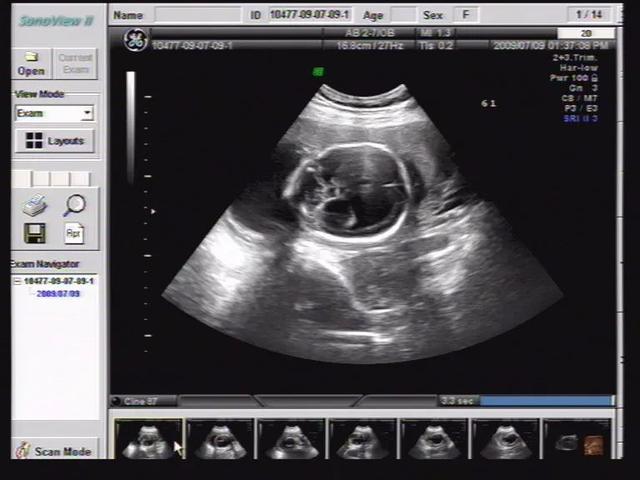

做b超时通过测量侧脑室的宽度来判断胎儿脑积水。侧脑室宽度超过1cm,常可发生脑积水。

胎儿发生脑积水后,需要进一步检查脑实质是否有器质性病变或其他结构畸形。建议孕期做MRI,进一步确定胎儿是否存在脑积水。

如果胎儿被诊断为脑积水,下一步的治疗要根据目前的胎龄和脑积水的具体程度来决定。如果是单一脑积水,就要看脑室是否继续扩大。一般积水量在1.5 cm以下,属于中度脑积水,产前检查各方面正常。有时并不影响出生后智能神经的发育,可以考虑留下,但要注意观察,定期进行三维或四维彩超复查。

如果胎儿侧脑室宽度大于1.5 cm,胎儿脑积水可能比较严重,通常需要产前诊断。如果产前诊断确诊为重度脑积水,一般建议及时引产。